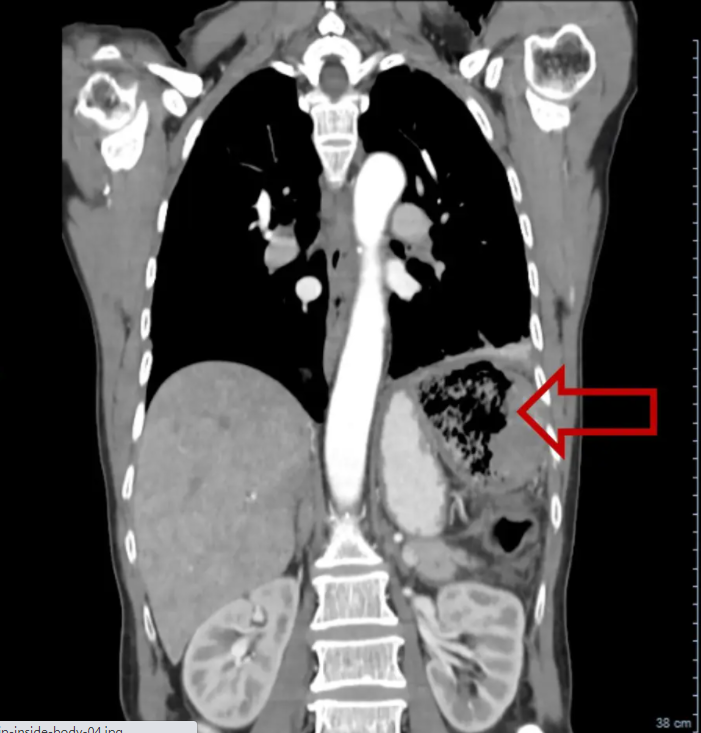

这名患者对突然出现的症状感到惊恐,于是赶紧去看医生。超声波扫描显示她的腹部有一大块纱布。医生们认为,这个黏糊糊的东西应该是在20多年前的手术中留在她的结肠里的。

为什么医院的纱布不卖纱布在身体里20多年!女子突然发烧、腹痛、掉秤 医院一查让人咋舌_https://www.jmylbn.com_新闻资讯_第6张

幸运的是,纱布没有在很难搞的地方,外科医生给她做了一个小手术,将这团纱布取了出来(上图)。

据图片显示,这团纱布看起来很硬,呈棕色,就像古代木乃伊的包裹。